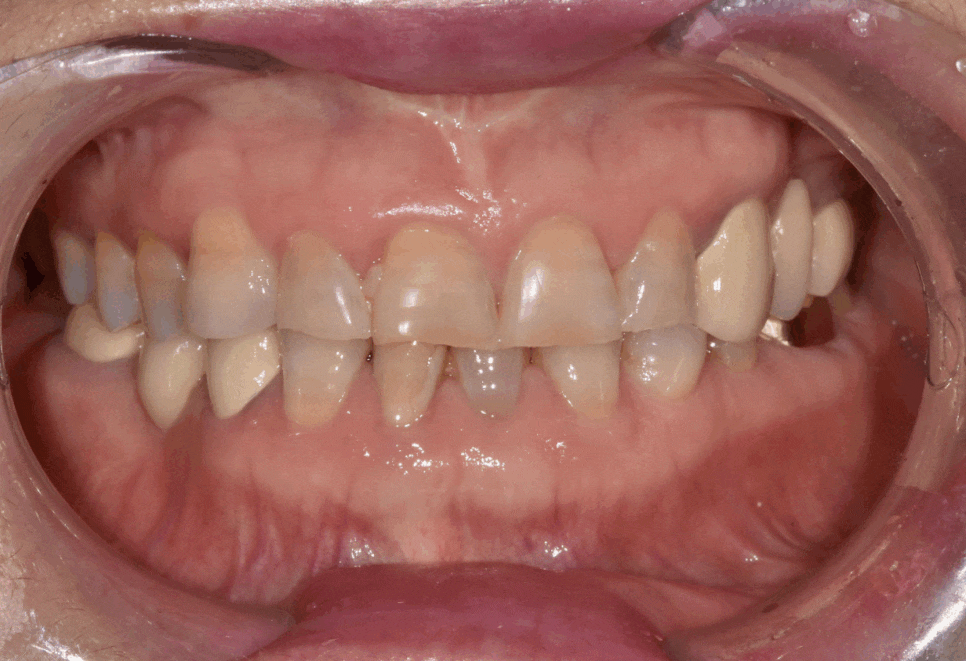

이 환자분은 누런 치아를 개선하기 위해

라미네이트를 문의하러 오셨습니다.

실제로 보니 치경부 쪽(치아와 잇몸 경계)이

전체적으로 어두웠습니다.

앞니 끝도 군데군데 깨져있었습니다.

환자분은 아래 앞니 2개와 작은 어금니 1개가 없는 상태였습니다.

230420 누런 치아 연예인치아 처럼 하얗게 만들 수 있나요?

그래서 정면에서 봤을 때 중앙선이 맞지 않습니다.

게다가 왼쪽 위와 오른쪽 아래 브릿지도 오래되어 교체가 필요한 상태입니다.